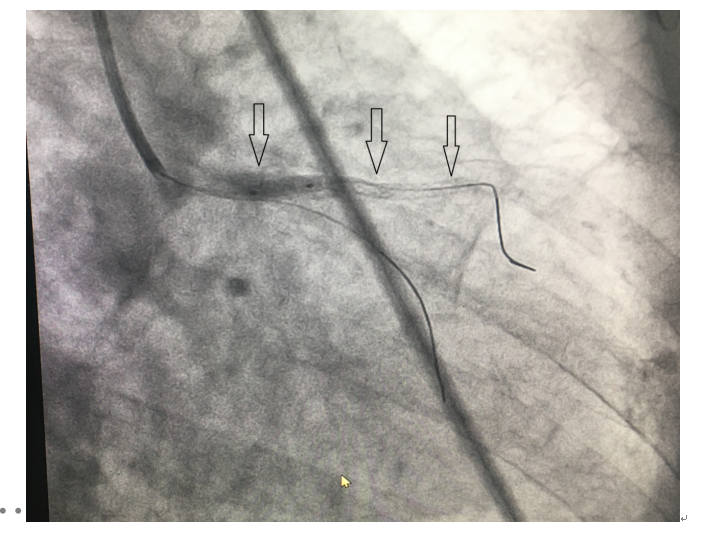

(三)支架植入